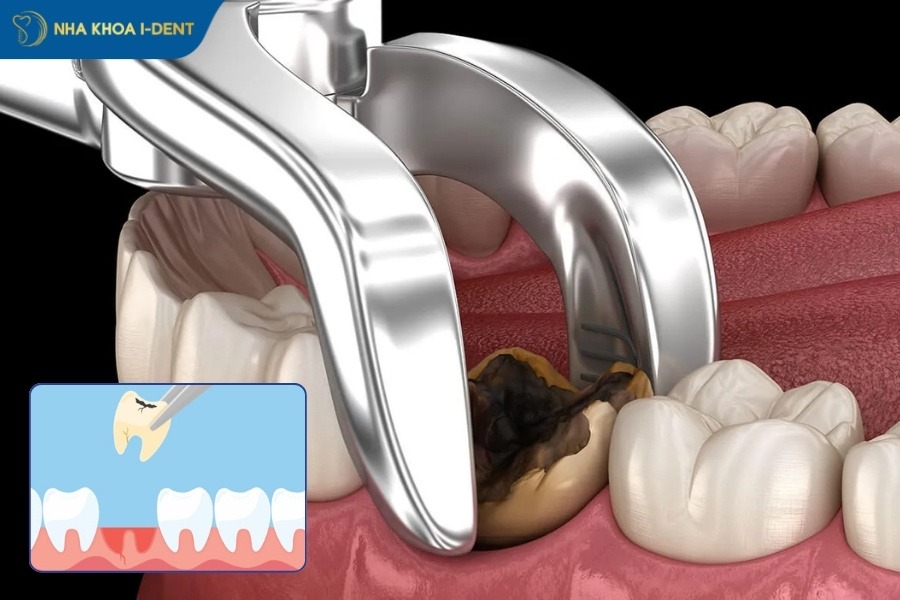

5.4. Nhổ răng

Khi thuốc tê ngấm hoàn toàn, bác sĩ sẽ tiến hành lấy dụng cụ chuyên dụng để làm lung lay chân răng và sau đó nhổ răng bằng máy Piezotome. Toàn bộ quá trình nhổ răng diễn ra rất nhanh chóng và không đau.

Nha khoa I-Dent nhổ răng bằng máy siêu âm Piezotome giúp hồi phục nhanh và ít xâm lấn.